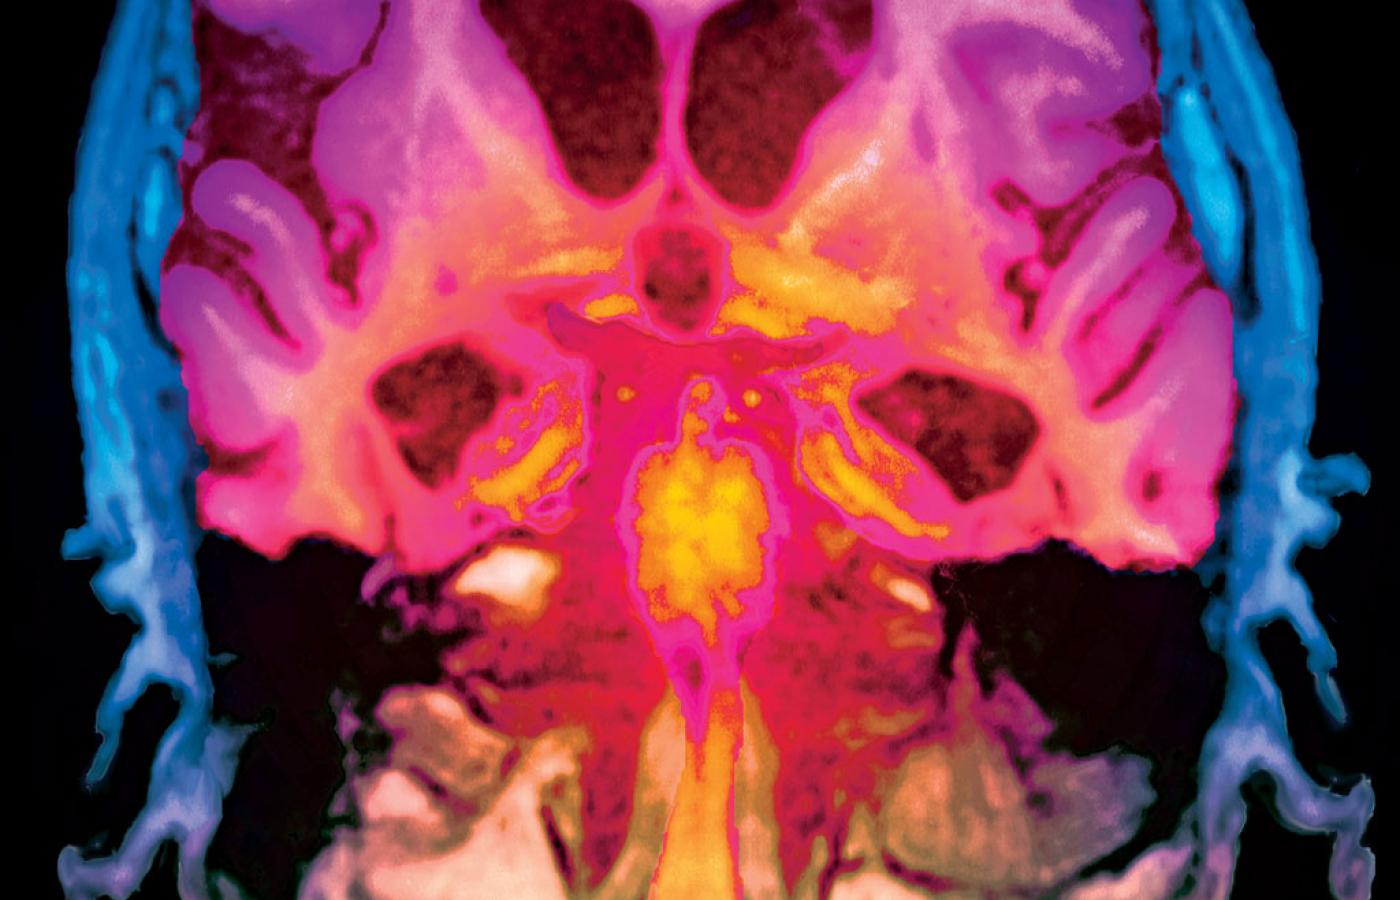

Sztucznie kolorowany obraz przekroju mózgu z objawami choroby Alzheimera uzyskany w rezonansie magnetycznymSovereign/BEW Sztucznie kolorowany obraz przekroju mózgu z objawami choroby Alzheimera uzyskany w rezonansie magnetycznym